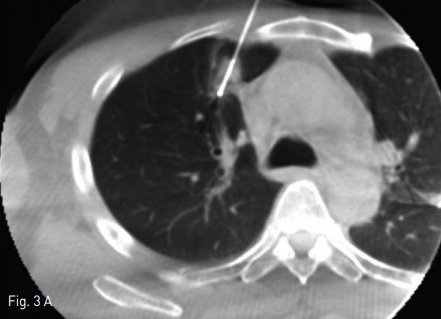

폐전이암 절제술 후 추적검사상 흉부 전산화 단층촬영에서 우측 폐 상엽에 0.7cm가량의 조영 증강되는 폐결절이 새롭게 관찰 되었다.(Fig. 1)

Fig 1A

Axial & coronal CT scan show a 0.7x0.5 cm sized enhancing solitary pulmonary nodule in right upper lobe.

Fig 1B